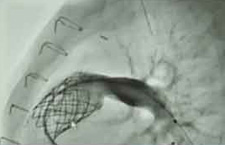

Kayla received one of the area’s first Medtronic Melody Heart Valves. The valve is inserted through a catheter in the groin to repair a damaged conduit. The conduit was surgically implanted when Kayla was a baby to correct blood flow from the heart. By successfully repairing the conduit with the new valve, inserted via transcatheter, Kayla was able to delay or avoid open heart surgery.

Approved by the FDA in February 2010, St. Louis Children’s Hospital is one of the first hospitals to implant the Melody Heart Valve. “It’s exciting for the patients and their families,” says Dr. Balzer.  “They do not look forward to a lifetime of repeated operations, so for them this is a big deal. And for us, it’s very exciting to be able to participate in that.”